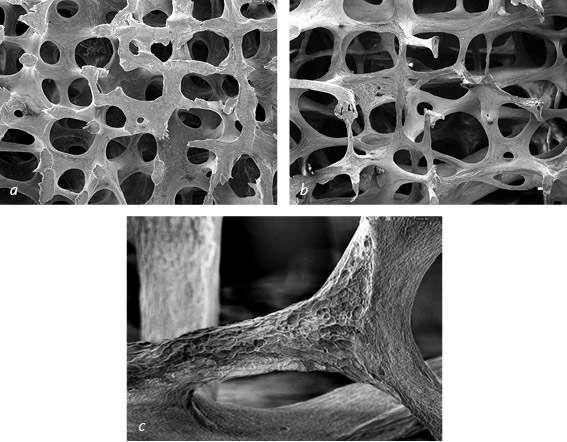

Иллюстрация к книге — Кости: внутри и снаружи [i_025.jpg]

На микрофотографиях, сделанных с помощью сканирующего электронного микроскопа, видна губчатая кость из поясничных позвонков. В норме ее структура представляет собой прочную упорядоченную сеть (a). Гормональные изменения и отсутствие механической нагрузки приводят к истончению и ослаблению губчатой кости – это указывает на остеопороз (b). Увеличение позволяет увидеть в пораженной остеопорозом кости воронки и рытвины, образованные разрушающими кость остеокластами (c)

Prof. Tim Arnett, Университетский колледж Лондона